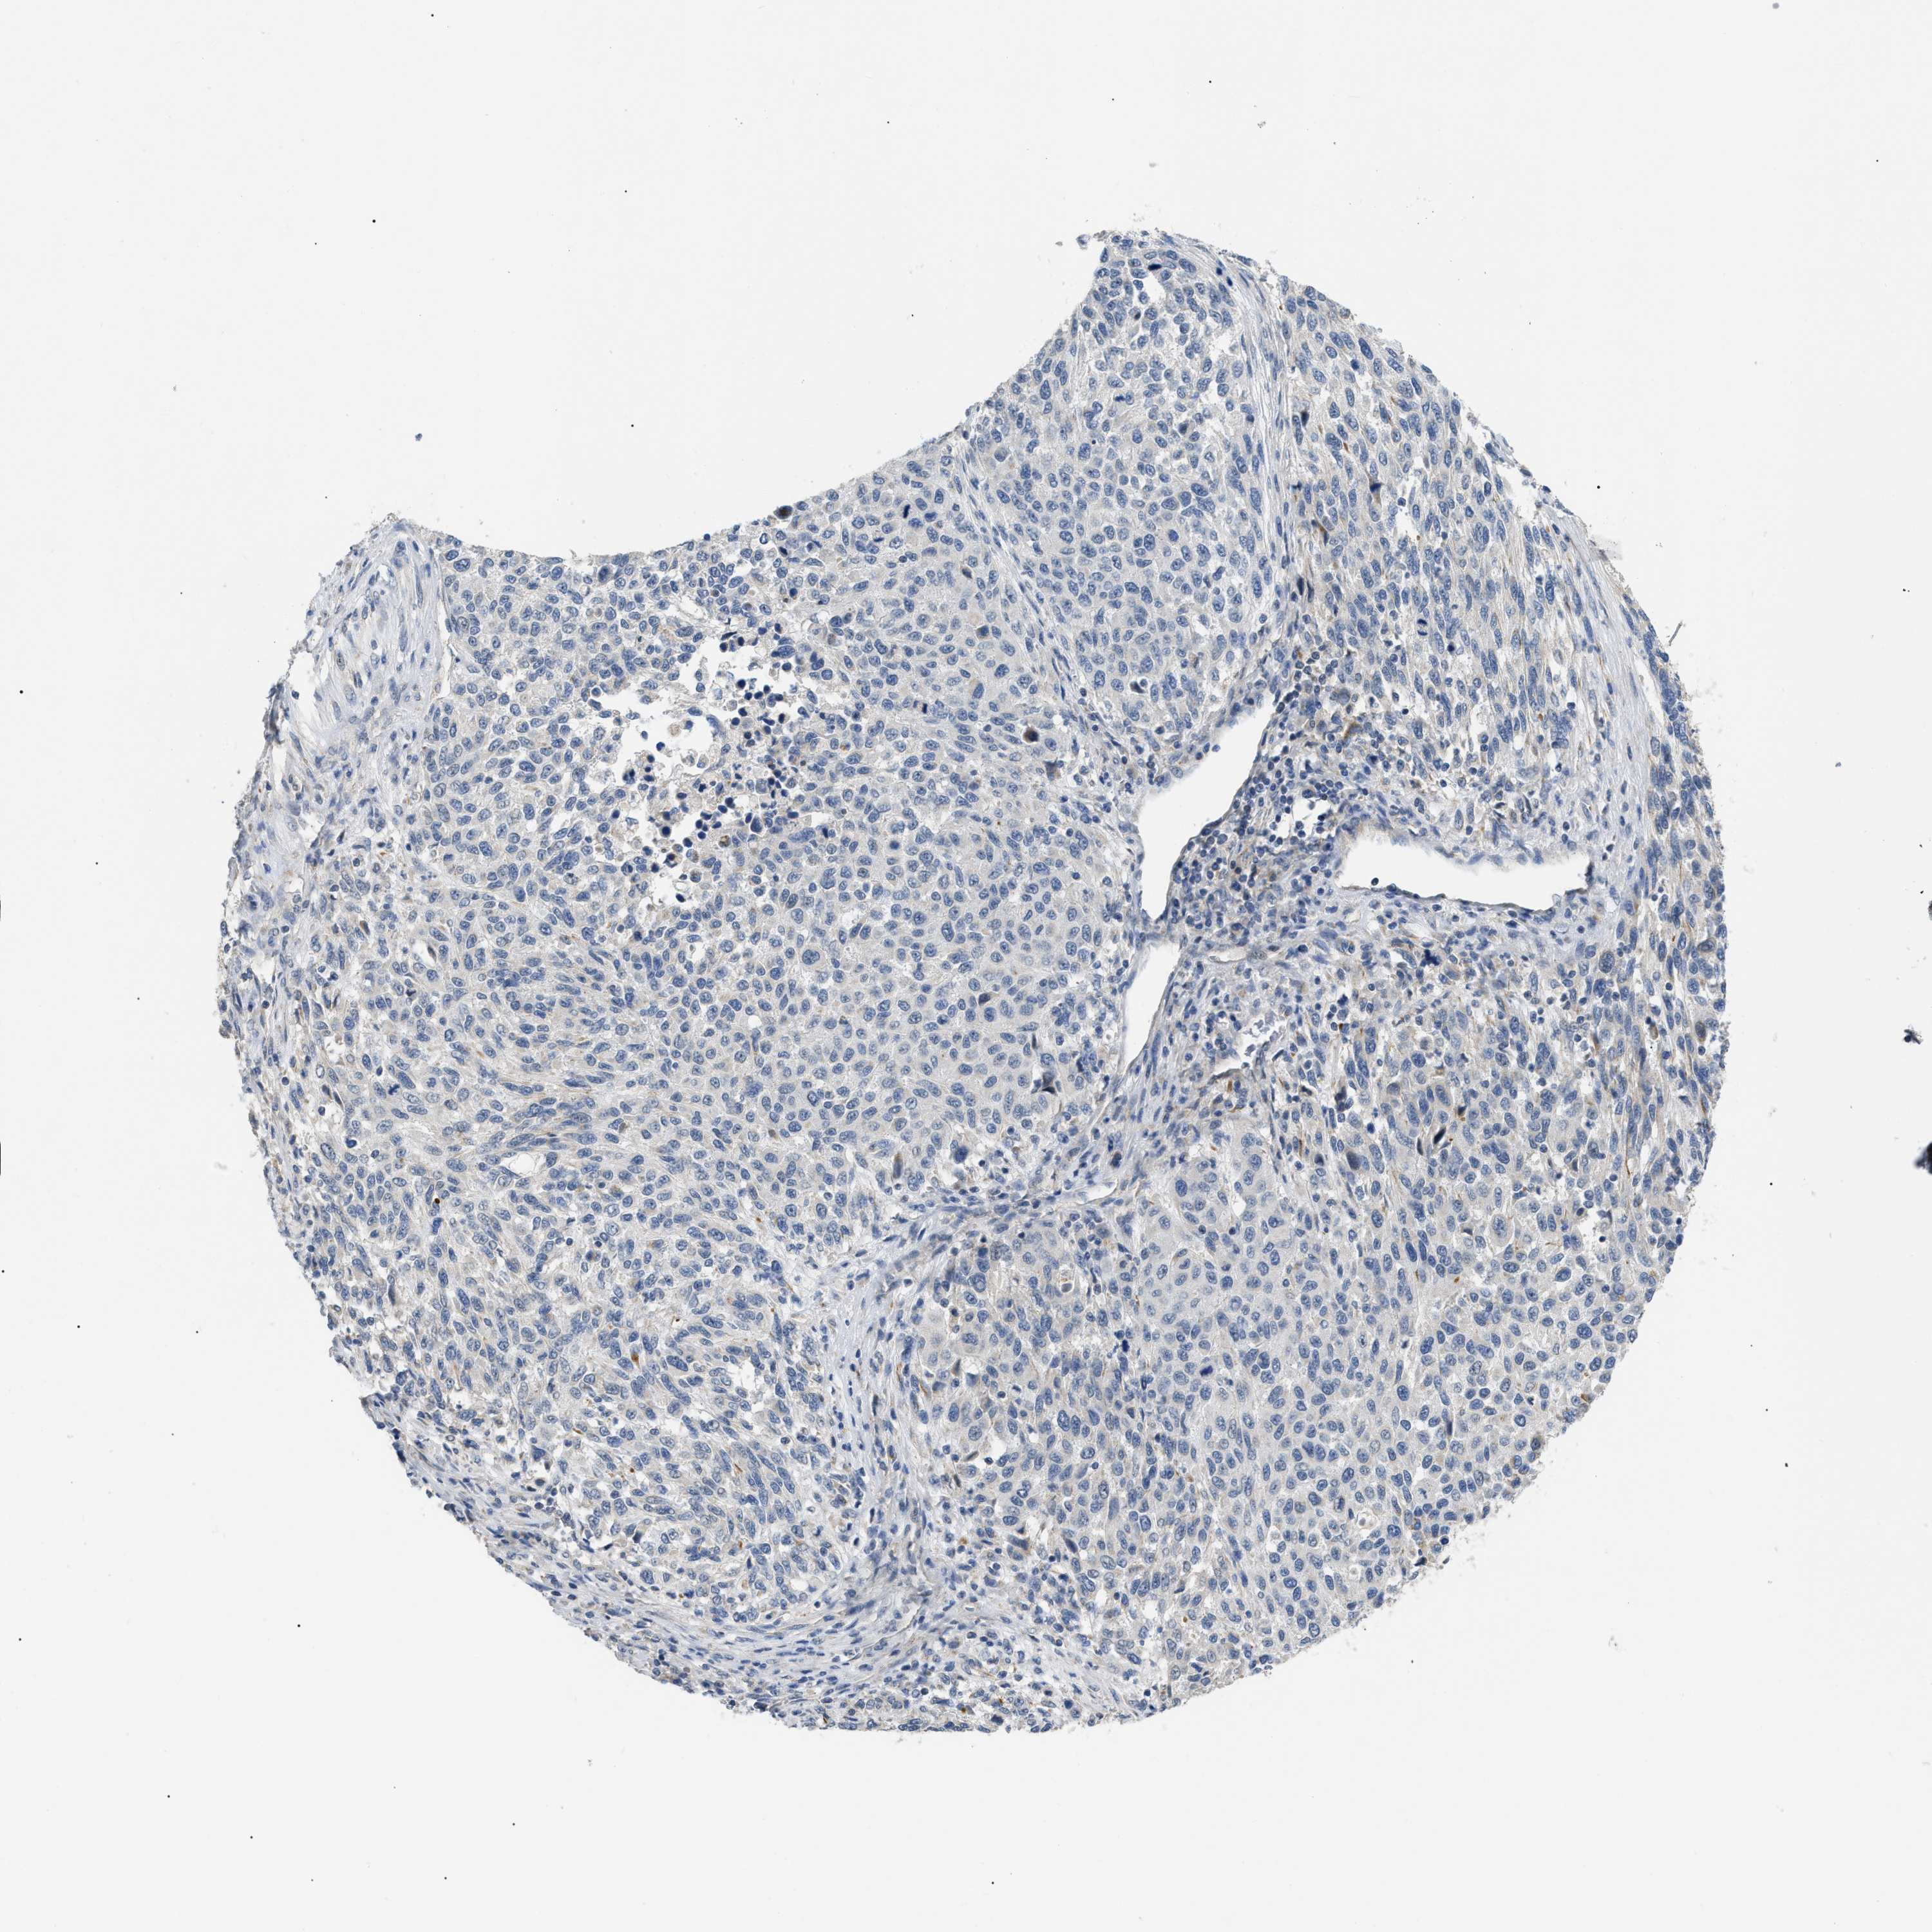

MELANOMA - Protein expressioni

A mouse-over function shows sample information and annotation data. Click on an image to view it in a full screen mode. Samples can be filtered based on level of antibody staining by selecting one or several of the following categories: high, medium, low and not detected. The assay and annotation is described here.

Note that samples used for immunohistochemistry by the Human Protein Atlas do not correspond to samples in the TCGA dataset.

Antibody stainingi

Antibody staining in the annotated cell types in the current human tissue is reported as not detected, low, medium, or high, based on conventional immunohistochemistry profiling in selected tissues. This score is based on the combination of the staining intensity and fraction of stained cells.

Each image is clickable and will lead to virtual microscopy that enables deeper exploration of all samples and also displays staining intensity scores, fraction scores and subcellular localization as well as patient and tissue information for each sample.

Antibody HPA018670

Antibody HPA019570

Staining

High

Medium

Low

Not detected

Intensity

Strong

Moderate

Weak

Negative

Quantity

>75%

75%-25%

<25%

None

Location

Nuclear

Cytoplasmic/membranous

Cytoplasmic/membranous,nuclear

Malignant melanoma, NOS

Malignant melanoma, Metastatic site